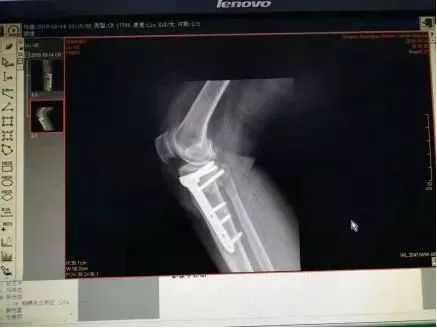

术后复查X片

术后双下肢全长片